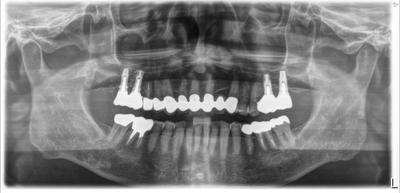

HOME > ブログ 一覧 > インプラント包括ケース 2021.02.05インプラント包括ケース インプラント包括ケース、術後16年。 メインテナンス中。 使用インプラントはBiomet 3i(アメリカ) 上顎インプラントにはソケットリフトによる骨移植を行っているが、元々患者さん自身の骨と同化し区別がつかない、、、というのは正確ではなく、置換されている。 Recent Entries アライナー矯正(インビザライン、シュアスマイル)費用を2023年 1月から改訂させていただきます(01/09) 本年もよろしくお願いいたします(01/02) 年始の診療について(01/01) 新しいWEBへ移行、年末年始の診療のお知らせ(12/29) ダラダラ根管治療行っても治らないという事(12/21) Category その他の治療(126) インビザライン・矯正(52) インプラント治療(216) ホワイトニング(47) メインテナンス(21) 包括診療(95) 医院からのお知らせ(249) 審美治療(128) 日々雑感(283) 根管治療(100) 歯周病治療(90) 矯正(73) 補綴治療(45) 補綴治療カテゴリを追加(1) 診療全般(44) Archive 2023年1月(3) 2022年12月(6) 2022年11月(14) 2022年10月(6) 2022年9月(8) 2022年8月(7) 2022年7月(13) 2022年6月(8) 2022年5月(7) 2022年4月(7) 2022年3月(6) 2022年2月(7)